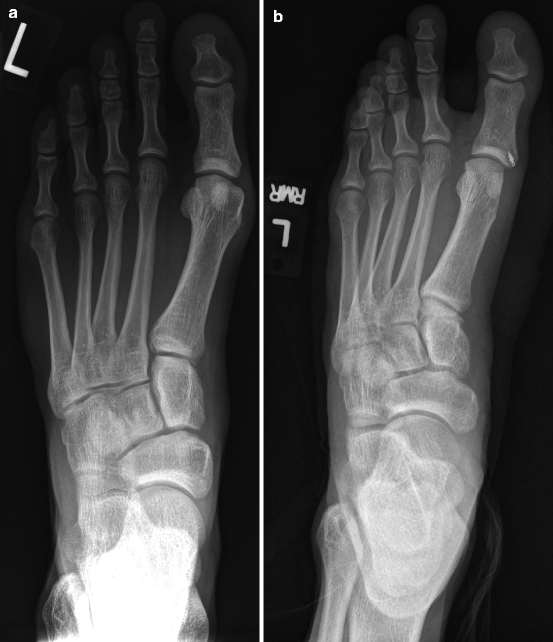

Grade 3 turf toe injury. Turf toe is a colloquial term for a condition in which the ligaments around your big toe become strained. The mechanism in typical turf toe injuries is one of extreme traumatic dorsiflexion (hyperextension), often with superimposed varus or valgus angulation, which causes disruption of the plantar plate capsuloligamentous complex and allows unrestricted range of motion of the first mtp joint. The packers' top target in the passing game is dealing with a turf toe injury he first suffered against the philadelphia eagles on sept. Turf toe can range from grade 1, not as serious, to. Turf toe occurs when the ligament underneath the big toe hyperextends, causing a sprain. Carbon fiber insole, rigid, shoe insert 1pc supportive orthopedic insert best for fractures, turf.

A turf toe injury has 3 major grades with different recovery time and treatment. Best big toe joint injury treatment. Turf toe can range from grade 1, not as serious, to. 27.09.2019 · adams' specific return timeline depends on the severity of the turf toe injury. It can also happen on a grass surface, especially if the shoe being worn doesn't provide adequate support for the. To help plan treatment for turf toe. This damage can occur when pushing down on the toe repeatedly puts stress on this part of the body. Fix it 100% satisfactorily with the right brace, splint and taping at home! With all grades there is usually some. The injury usually happens when the foot sticks while the rest of the body continues forward. Turf toe occurs when the ligaments around the big toe joint become sprained, causing pain, stiffness, and reduced mobility. Grade 3 turf toe injury. Turf toe occurs when the ligament underneath the big toe hyperextends, causing a sprain. Pain can usually be felt immediately at the time of injury but may get worse over time as the swelling increases. 🦶turf toe is caused by a hyperextended big toe joint.🦶 this can lead to a turf toe injury that can have 3 grades. Often a complete and systematic evaluation of all the structures of the great toe joint is not performed. The ligaments that connect the big toe to the ball of the foot are complex, and are essential to the moves involved in walking, running, jumping, and quickly immediately after the injury occurs or becomes noticeable, the athlete should stop running and jumping for the time being. Most cases resolve with rest alone, but some severe injuries may require surgery. Mahomes will reportedly play through the turf toe injury in super bowl lv before having offseason surgery to repair it. Turf toe is a colloquial term for a condition in which the ligaments around your big toe become strained. The mechanism in typical turf toe injuries is one of extreme traumatic dorsiflexion (hyperextension), often with superimposed varus or valgus angulation, which causes disruption of the plantar plate capsuloligamentous complex and allows unrestricted range of motion of the first mtp joint. Turf toe injury can also develop gradually from repetitive, forced jamming through the big toe such as with quick pivoting, accelerating and jumping. Artificial turf is the perfect material for a foot to stick to. A turf toe injury has 3 major grades with different recovery time and treatment. Carbon fiber insole, rigid, shoe insert 1pc supportive orthopedic insert best for fractures, turf. An inaccurate diagnosis could lead to ineffective and unsuccessful treatment, wasting a great deal of your time and money. The term turf toe refers to an injury of any soft tissue structure in the plantar complex, such as the plantar plate or a collateral ligament. Unfortunately, many times, any injury to the great toe joint that occurs during a sporting event is erroneously termed turf toe. A turf toe taping technique will support and protect the toe preventing it from bending in the direction that will stress the ligament causing pain. It happens most often in football players, but it can. Turf toe is a sprain of the big toe joint resulting from injury during sports activities.